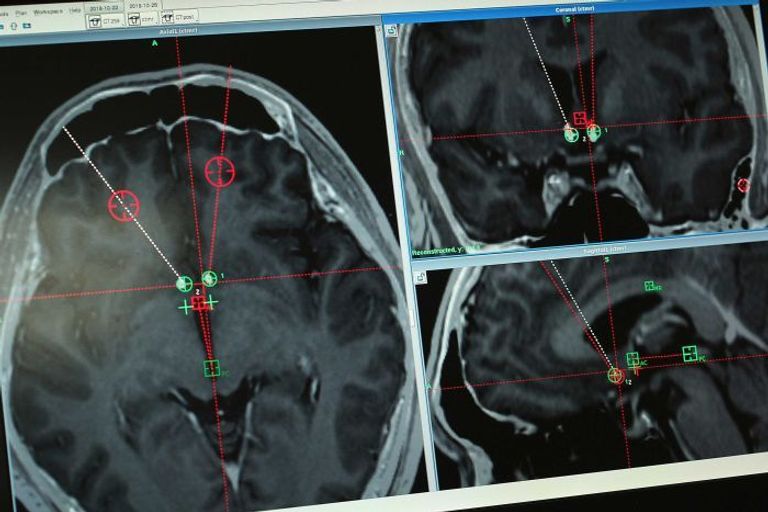

وتتضمن هذه التقنية، التي اُستخدمت منذ فترة طويلة لعلاج اضطرابات الحركة مثل مرض باركنسون، حفر فتحتين صغيرتين في جمجمة المريض، ووضع أقطاب كهربائية في عمق الدماغ.

وفي أكتوبر/تشرين الأول، قام الطبيب لي بمستشفى رويجين في الصين، بعملية حفر لجمجمة المريض يان، وغرز قطبين كهربائيين إلى قاعدة الدماغ الأمامية المسؤولة عن تحفيز الشعور بتعاطي المخدرات، وبعد ساعات خضع المريض لعملية ثانية لزرع بطارية في صدره لتشغيل الأقطاب الكهربائية في جمجمته، وفقاً لشبكة أخبار "جوان تشا" الصينية.